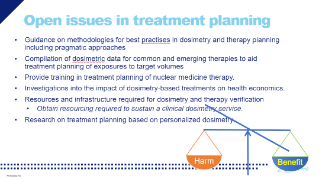

Dosimetry-guided treatment planning in Nuclear Medicine

Oct 08, 2020

External Link( 96.0 KB )

Prof. Mark Konijnenberg shares how dosimetry-guided treatment should provide the right balance between harm and benefit; eg low toxicity and increased survival.